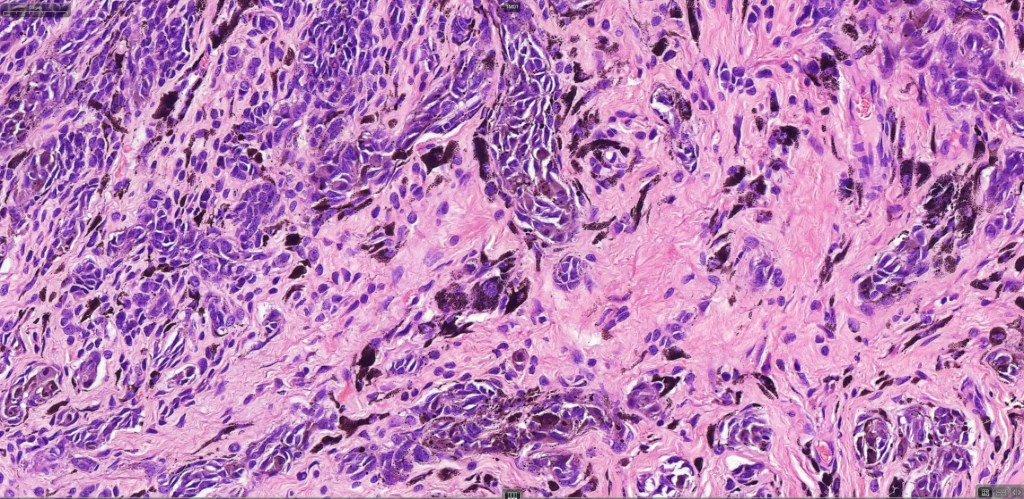

This is uncommon and presents clinically with a history of recent change in color of a common or less often congenital nevus causing concern for melanoma by the clinician. Some, but not all are probably deep penetrating and combined nevus variants. Others may represent follicular type-A cell nests. It is characterized by the presence of deep nest(s) of type -A nevus cells surrounded by & with overlying type-B nevus cells.